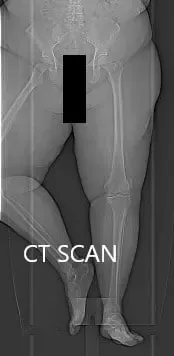

Topographic CT images of the weight-bearing Right and Left knee respectively.

A few weeks prior, a CT scan of the bilateral lower extremities was performed to obtain detailed data on the patient’s unique anatomy and biomechanics of the knees. A preoperative plan was formed to guide the surgeon in bone cuts and offsets. Disposable instruments were custom made for the patient. Unique customized implants were made to match the patients cut surface of the knee.